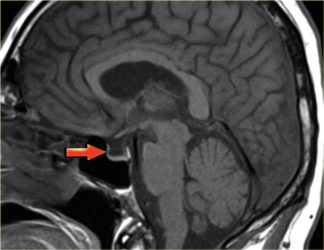

МРТ у пациента, страдающего несахарным диабетом

Как известно, причиной этой патологии является дефицит гормона вазопрессина, который в норме вырабатывается клетками гипоталамуса, оттуда попадает в гипофиз, а из него – в кровь. Вызвать недостаточность гормона может воспалительный процесс в области гипоталамо-гипофизарной системы или же ее опухоль. Признаки обеих патологий будут видны на томограмме.

При идиопатическом несахарном диабете (природа которого неясна) МРТ позволит обнаружить, что гиперинтенсивный сигнал от нейрогипофиза (задней доли этой железы) на Т1-ВИ отсутствует.

СТГ-недостаточность на МРТ

При дефиците соматотропного гормона на томограмме будут обнаружены 1 или несколько из нижеуказанных признаков:

- характерная триада – эктопия (расположение клеток в нетипичном месте) нейрогипофиза, гипоплазия (недоразвитие) аденогипофиза (то есть передней его доли), гипоплазия или аплазия (врожденное отсутствие) ножки гипофиза (признак имеет место в 40 % случаев патологии);

- гипоплазия гипофиза (диагностируется почти у трети пациентов);

- признаки синдрома пустого турецкого седла (описаны выше; обнаруживаются у каждого пятого больного).

У 10 % пациентов патологические изменения области гипофиза вообще отсутствуют.